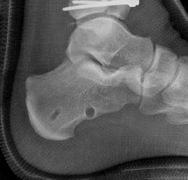

A profound understanding of the distal tibia's surgical anatomy and the biomechanical principles of fracture fixation is non-negotiable for the operating surgeon. The distal tibia expands from a triangular diaphyseal cross-section to a rectangular metaphyseal flare, culminating in the articular plafond. The plafond itself is anatomically divided into three primary columns or fragments: the medial malleolus, the anterolateral (Chaput) fragment, and the posterior (Volkmann) fragment. The syndesmotic ligamentous complex binds the distal tibia to the fibula, playing a critical role in ankle mortise stability. In high-energy axial load injuries, the talus acts as a hammer, driving upward into the plafond and causing central impaction and comminution that is often devoid of soft tissue attachments.

The first objective of the internal fixation phase is the anatomic reconstruction of the articular block. The joint capsule is incised to allow direct visualization of the plafond. A femoral distractor or a temporary external fixator spanning the joint can be utilized to gain joint space and visualize the central impacted fragments. Using a dental pick or a Freer elevator, the central die-punch fragments are carefully disimpacted and brought down flush with the talar dome.

Once the articular surface is visually and fluoroscopically reduced, the resultant metaphyseal void is densely packed with cancellous allograft, autograft, or synthetic bone substitute to prevent late subsidence. The major articular fragments (Chaput, Volkmann, and medial malleolus) are then reduced around the central reconstructed block using pointed reduction forceps. Provisional fixation is achieved with multiple 1.6mm or 2.0mm Kirschner wires. Independent 3.5mm or 4.0mm lag screws can be placed outside the planned footprint of the definitive plate to secure the articular block.